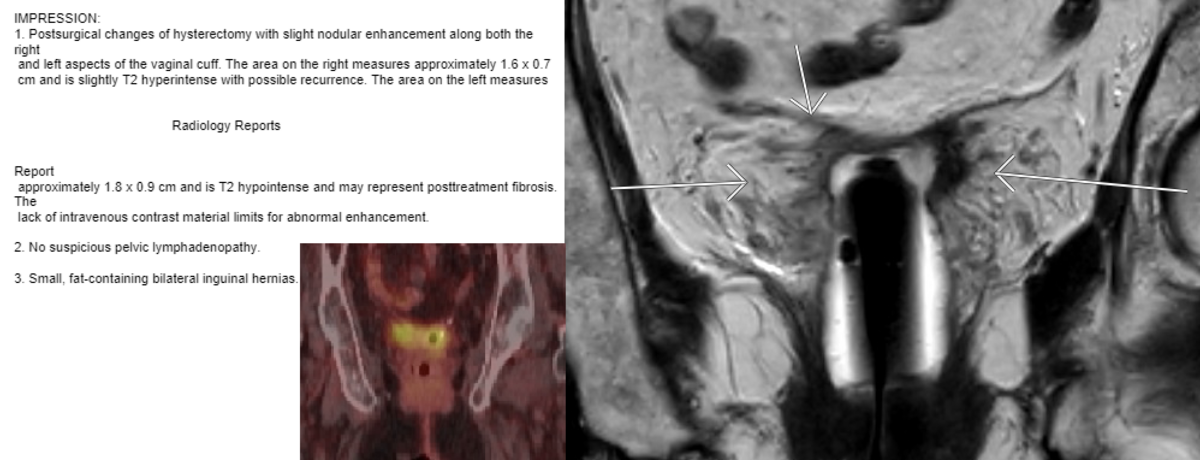

I had a similar case Last year. Pt is a 84-year old female with cervical cancer diagnosed in 1990 treated with Pelvic RT and LDR Intracavitary Brachytherapy. In 1996 she had hysterectomy for persistently positive PAP smears. No issues till Jan 2020 when she presented with vaginal bleeding and diagnosed with Squamous cell carcinoma.

PNG image 2.png

Workup showed disease confined to upper vagina as shown above. Pt was treated with Cs-131 interstitial, single plane free seed implant in Jan, 2020 To a dose of 50Gy prescribed to 5mm depth.

She remains no evidence currently with obliteration and narrowing of upper vagina as shown in the following pic.

Your patient looks like she would be a good candidate for Cs-131 interstitial seed single plane implant to a dose of 50-55Gy. Cs-131 interstitial implant in previously radiated patients is safe as it limits volume of re-irradiation to just upper vagina which has high tolerance with radiation.